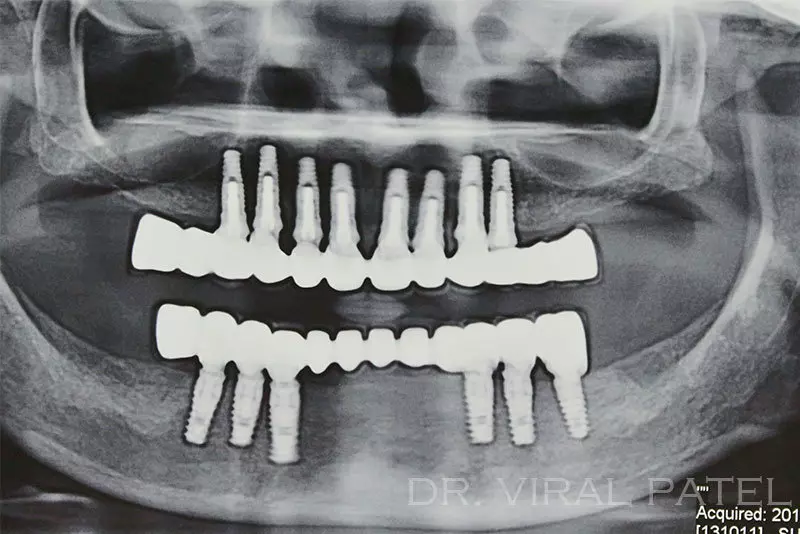

The second technique involves the use of CT [Computed Tomography] Studies. This allows a very detailed assessment in three  dimensions.

These 3 dimentional raw images run in a deisigning software and a surgical templates prepared with the anticipatory ideal dental implant positions with a cad cam technology. Specialized computer software enables implant surgeons to assess all of the critical areas of the maxillary and mandibular bone structures. The precision imaging helps dentists to not only determine the best possible implant sites but also permit the assessment of need for bone augmentation (grafting) that will optimize predictability ratios.

The entire procedure of assessment, treatment planning, selection of implant systems and final prosthesis  planned “virtually” before treatment begins. Patients benefit from being able to visualize, fully, current state of need and final outcome possibilities, based on their choice of restoration components (types of crowns, abutments, shape, color shading, size, etc).